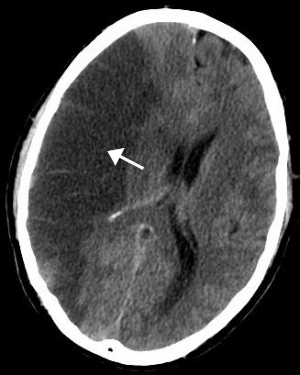

두통

- 갑작스러운 심한 두통

- 원인 모를 갑작스러운 심한 두통이 발생하는지 확인하세요. 특히 평소 경험하지 못한 두통이라면 즉시 병원을 방문해야 합니다.